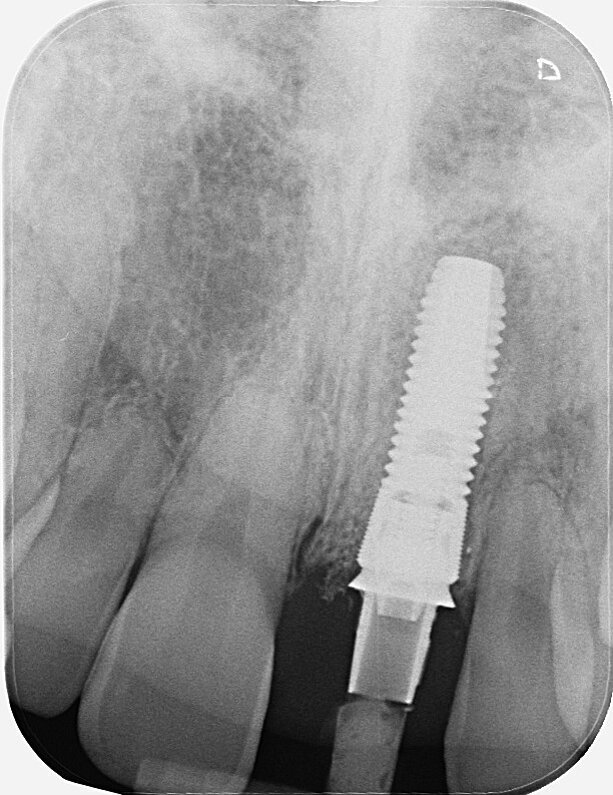

Fig. 19: Ideal osseointegration four months post-op.

For implants in the anterior tooth region, I produce long-term temporaries with CEREC. They have the significant advantage in that they do not look like temporaries, do not feel like temporaries to patients, and thus ensure better quality of life. The patients are also convinced of this. The follow-up radiograph (Fig. 19) before the final restoration with a custom-veneered ceramic crown showed good osseointegration of the implant. The gingivae were externally completely free of inflammation.